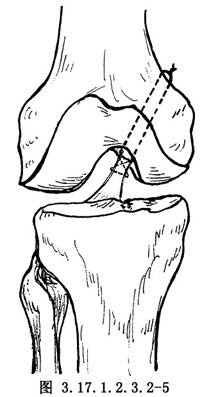

首先找出後交叉韌帶撕脫端,用不鏽鋼絲縫合韌帶斷端,近髁關節緣、股骨內側髁外側面,在韌帶附着部,用7.5mm粗的鑽頭經皮質鑽一凹陷區域。在凹陷區內用克氏針對向股骨內上髁上方,鑽兩個相距1cm平行的骨孔;如不方便可從股骨內上髁的上方向內鑽。韌帶斷裂端的縫合鋼絲分別通過骨孔,在保持脛骨向前拉的位置下,鋼絲在持續張力下做膝關節0°~90°範圍內的屈曲運動,檢查固定位置是否合適,如有韌帶太緊張、滑動或出現伸屈受限的情況,應加以調整,張力適當後,鋼絲在內上髁的兩個鑽孔的骨橋上打結(圖3.17.1.2.3.2-5)。